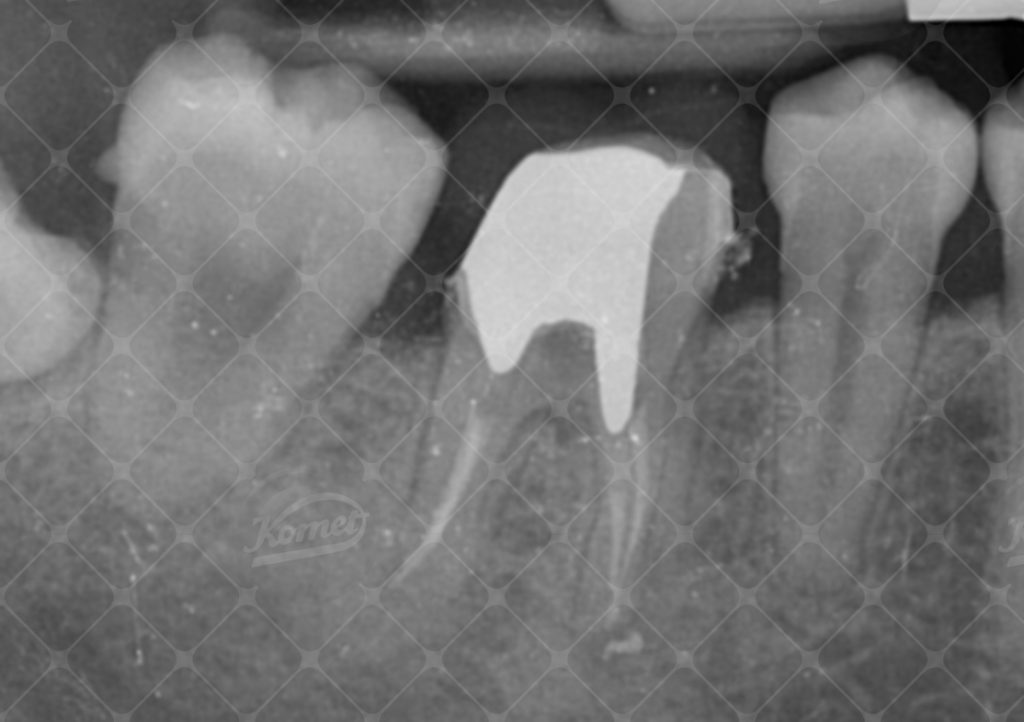

Al fine del recupero dell’elemento dentario, un primo molare del quarto quadrante è stato sottoposto a terapia endodontica e successiva ricostruzione con perno moncone in lega preziosa. La valutazione parodontale evidenzia una distanza dal margine di tessuto dentale sano al livello osseo marginale sul versante interprossimale distale di 2 mm, insufficiente a garantire il cerchiaggio con effetto ferula della futura corona protesica ne’ tantomeno a consentire il costituiti di una fisiologica altezza di ampiezza biologica (Fig 1,2).